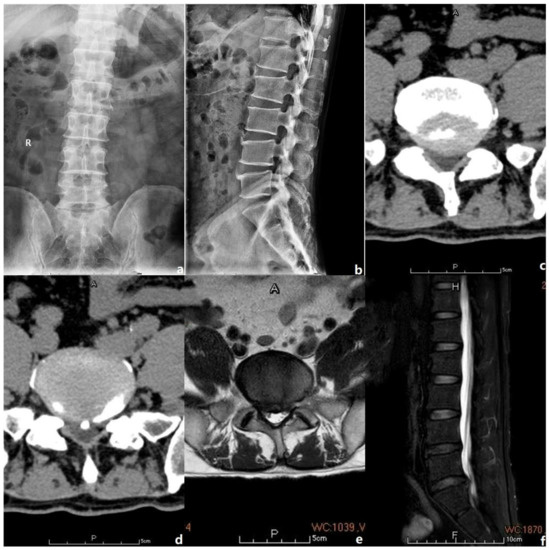

Informed consent was obtained from the patient and his relative before starting the treatment. The study was reviewed by the ethics committee of the corresponding author’s affiliated institution (approval no. NT-7964). Informed consent was obtained from all candidates before their participation in the study. Hence, in this article, a 54-year-old male patient presenting with right L5-S1 radiculopathy that corresponded to the image revealed on medical imaging and signs observed upon physical examination is reported (Figure 1). After completing the preoperative laboratory examination, which revealed that the patient’s coagulation was normal, an endoscopic L5/S1 laminectomy and discectomy were performed. An arterial ultrasonic doppler was also used before surgery to exclude preoperative thrombus formation in the lower limbs. The endoscopic decompression proceeded via continuous irrigation with a flow rate of 150 mL/min. The surgeon was young and a novice, with no more than ten cases of experience in spinal endoscopic surgery. Hence, while performing the surgery, coping with a calcified herniated disk, which caused a small-sized dural tear resulting in CSF leakage, was challenging for him (Supplementary intraoperative Video S1: https://www.dropbox.com/s/joj0uos7vgac2aw/modified%20video.mp4?dl=0) (Accessed date: 1 January 2023). Subsequently, the surgery was extended for another 1 h by an experienced endoscopic surgeon to rectify the complication. Moreover, to acquire a clearer surgical view, the flow rates for the irrigation fluid were increased up to 250 mL/min. The total operative duration was 1.5 h.

Figure 1.

The preoperative images of the case. The letter R, A, P, F, H in the figures refers to Right, Anterior, Posterior, Foot and Head, respectively. (a,b) Preoperative anterior and posterior lumbar spine radiographic films. (c,d) Preoperative lumbar CT scan showed L5/S1 canal stenosis with calcified disc protrusion. (e,f) Preoperative lumbar MRI manifested L5/S1 canal stenosis with disc herniation.